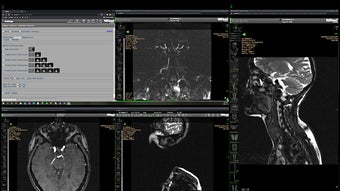

Hyland Clinician Fönster WinMan